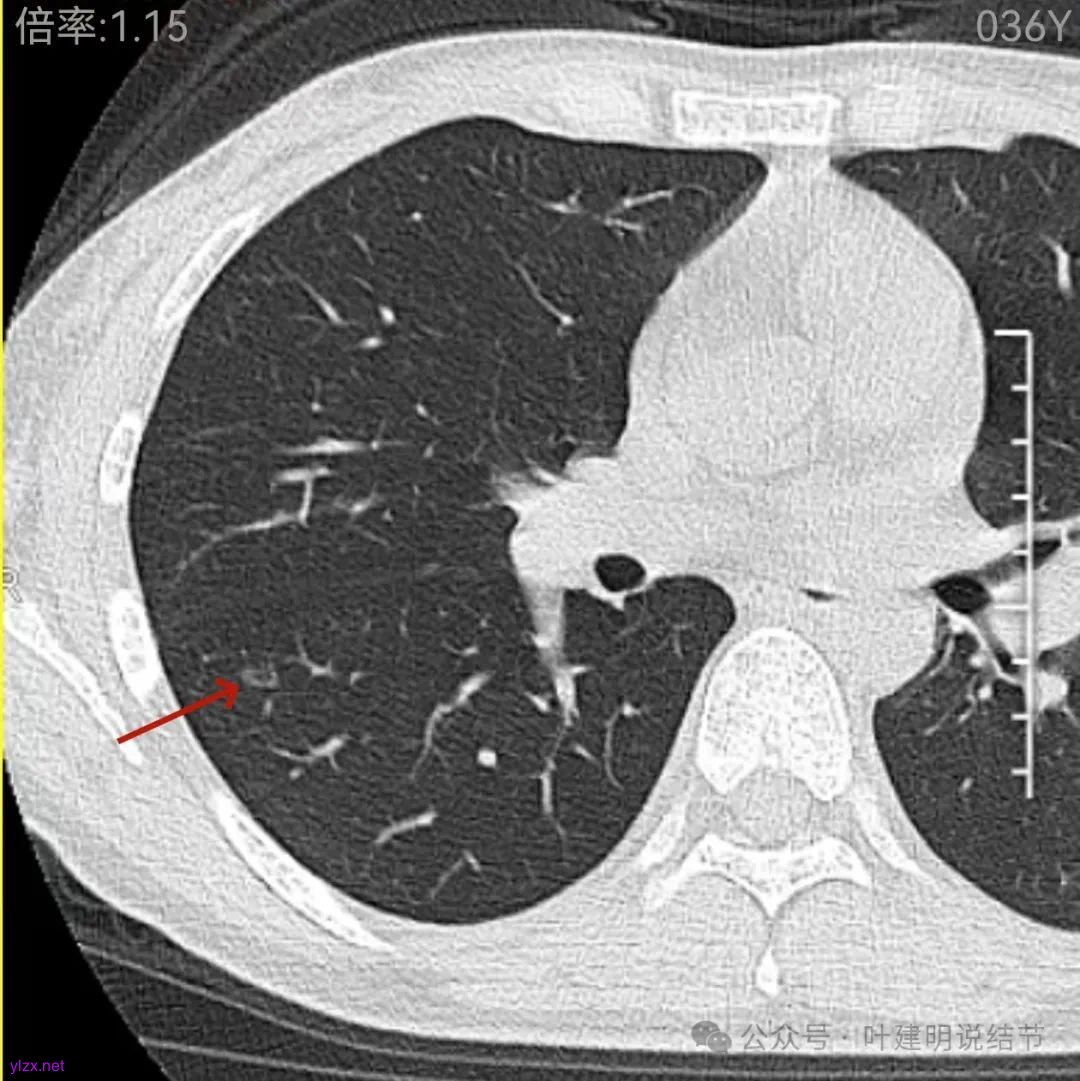

再看2022年9月的影像:

左肺尖病灶当时也有,没有明显变化。

左上叶此处当时也有,只是没有2024年轮廓与边界那么清楚,而且范围也是当时小点的。

再看中间2023年的影像:

左肺尖病灶相仿。

左上此灶2023攫与2022年时均较小,范围在2024年略有增大,显明显点。

右下此灶2023年时此层面淡而边显糊。

上图层面已经像混合密度了,表面毛糙不光滑,灶内密度不均,也有小空泡征的样子。

感觉这处(在上截图结节的下面点,邻近层面)不像前面病灶的延伸,否则这密度的变化有点突兀呀。

两肺多发结节,左侧黄色标注的考虑是肺泡上皮增生可能性大;蓝色的考虑肺泡上皮增生或者少许慢性炎可能性大;右侧红色宽起来并带有红色箭头的这处是主病灶,偏混合密度,整体轮廓较为清楚,边缘显得毛糙,从2024年12月份的来看,要考虑是肿瘤范畴,原位癌或者微浸润性腺癌可能性较大,也不能完全排除不典型增生。但是在2022年的时候,这个病灶的边上也有一个实性的微小结节,如果只看2022年的,这么小的实性结节,又比较圆,表面也显得较为光滑,是要考虑良性的,当然太小了需要动态观察。回头再重新来看2024年底的,发现绿色箭头所指的这个微小实性的较2022年几乎没有变,去仔细寻找2022年的,发现当时在实性结节旁边也有密度很淡的一点磨玻璃影(也可能真的就是一处,只是扫描不够薄,密度的变化有些突兀而已),而到了2024年12月份,实性微小这处没有明显变化,但是原来很淡的磨玻璃变成了混合磨玻璃,范围也明显扩大。所以总体来看右肺下叶这处是考虑恶性的,而且从磨玻璃结节角度来讲,还是生长比较快的,就是说还是有一定风险的。加上左侧还有两处也是磨玻璃持续存在,虽然边缘轮廓显模糊一点,但多年以后也可能仍然要变成原位癌或者微浸润性腺癌之类的东西。通盘考虑以后,我倾向于右侧近期单孔胸腔镜下微创局部切除,左侧随访观察,等到有进展并风险增加再来考虑处理。意见供参考!